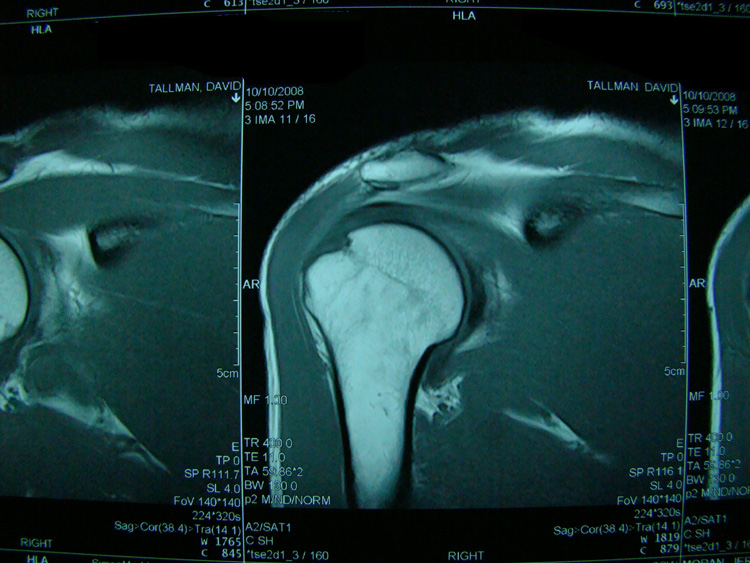

This patient presented with shoulder pain that interfered with work and exercise. The visible fluid-filled cysts on the “Before" MRIs are from chronically injured rotator cuff tendon roots.

The patient underwent treatments of a highly specialized fine-needling technique pioneered by Dr. Tallman.The follow-up MRI was done 2 months after his 6th treatment. He was released with a pain-free, full range of motion with unrestricted activities.